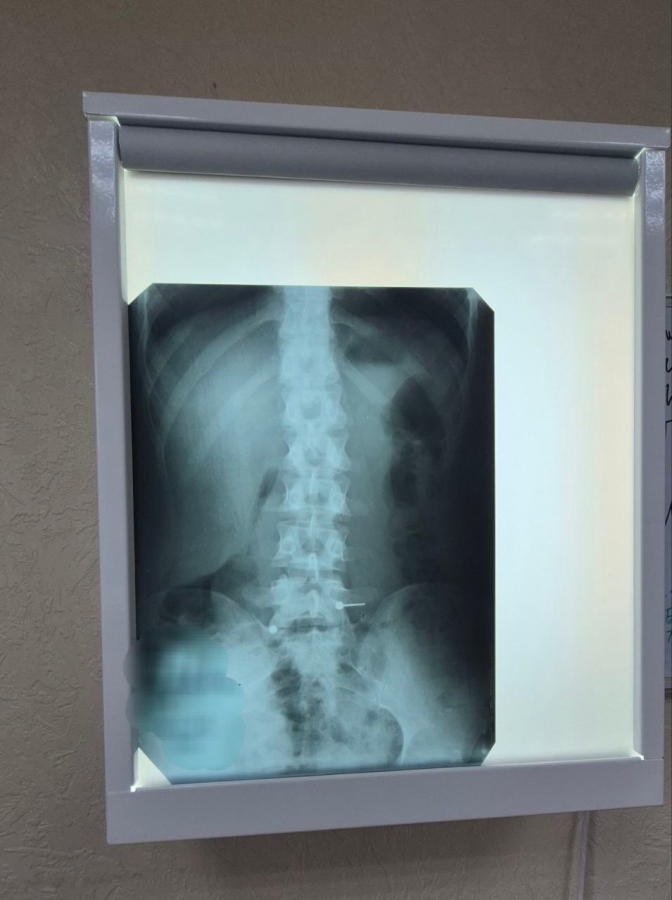

Девушка обратилась в стационар не сразу, а когда раскрутившиеся металлические части (шарик и штанга) уже покинули желудок и переместились в тонкий кишечник. Это сделало эндоскопическое извлечение без рисков осложнений невозможным.

Во втором случае в стационар попал двухлетний малыш, который, со слов мамы, примерно за час до обращения проглотил саморез. При каких условиях произошел инцидент, выяснить не удалось. Рентген подтвердил наличие острого металлического предмета внутри ребенка.

Саморез, к счастью, расположился шляпкой вниз, а острой частью вверх, что позволило предотвратить повреждение стенок желудочно-кишечного тракта и слизистой желудка. Благодаря этому удалось избежать необходимости проведения сложного открытого оперативного вмешательства. Мама ребенка отказалась от дальнейшей госпитализации, а малыш выписан под амбулаторное наблюдение. Саморез теперь войдет в коллекцию эндоскопистов больницы, в которой уже десятки самых необычных предметов.